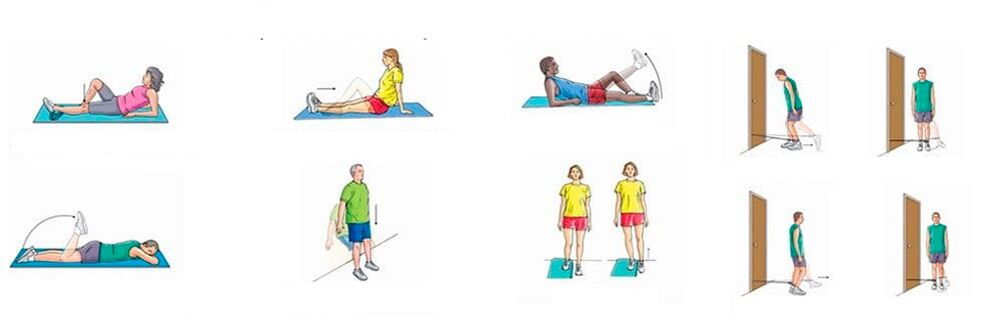

Con il dolore cronico alle articolazioni del ginocchio, quando non è presente un'infiammazione significativa, è possibile eseguire esercizi fisici che rafforzano il sistema muscolo-legamentoso, migliorano la circolazione sanguigna e il metabolismo. L'allenamento sistematico porta ad una graduale diminuzione del dolore, nonostante le gambe siano piuttosto croccanti.

Una serie approssimativa di esercizi per il dolore al ginocchio:

- Ginocchio fisso. Sdraiati sulla schiena, piega una gamba al ginocchio, sollevala e mantienila in questo stato per un minuto; la seconda gamba in questo momento è immobile; raddrizzare e abbassare la gamba molto lentamente, riposare per 10 secondi e ripetere l'esercizio con l'altra gamba; ripetere 10 volte;

- Piegamenti doppi delle gambe con le ginocchia vicino al viso. Sdraiati sulla schiena, piega le gambe sui fianchi e sulle ginocchia, fissa queste ultime vicino al viso e tienilo così per un minuto. Quindi raddrizza e abbassa lentamente le gambe, riposa per 10 secondi e ripeti; esegui 5-6 approcci, aumentando gradualmente il carico.

Il dolore acuto al ginocchio richiede uno stato di riposo; tutta l'attività fisica e l'allenamento sono controindicati.

In caso di dolore acuto all'articolazione del ginocchio, accompagnato da gonfiore e arrossamento della pelle, violazione delle condizioni generali, febbre, non è possibile muovere la gamba, deve essere tenuta a riposo. E solo dopo che l'infiammazione inizia a diminuire, è possibile passare prima agli esercizi passivi (eseguiti da un assistente) e poi agli esercizi attivi (eseguiti dal paziente stesso).